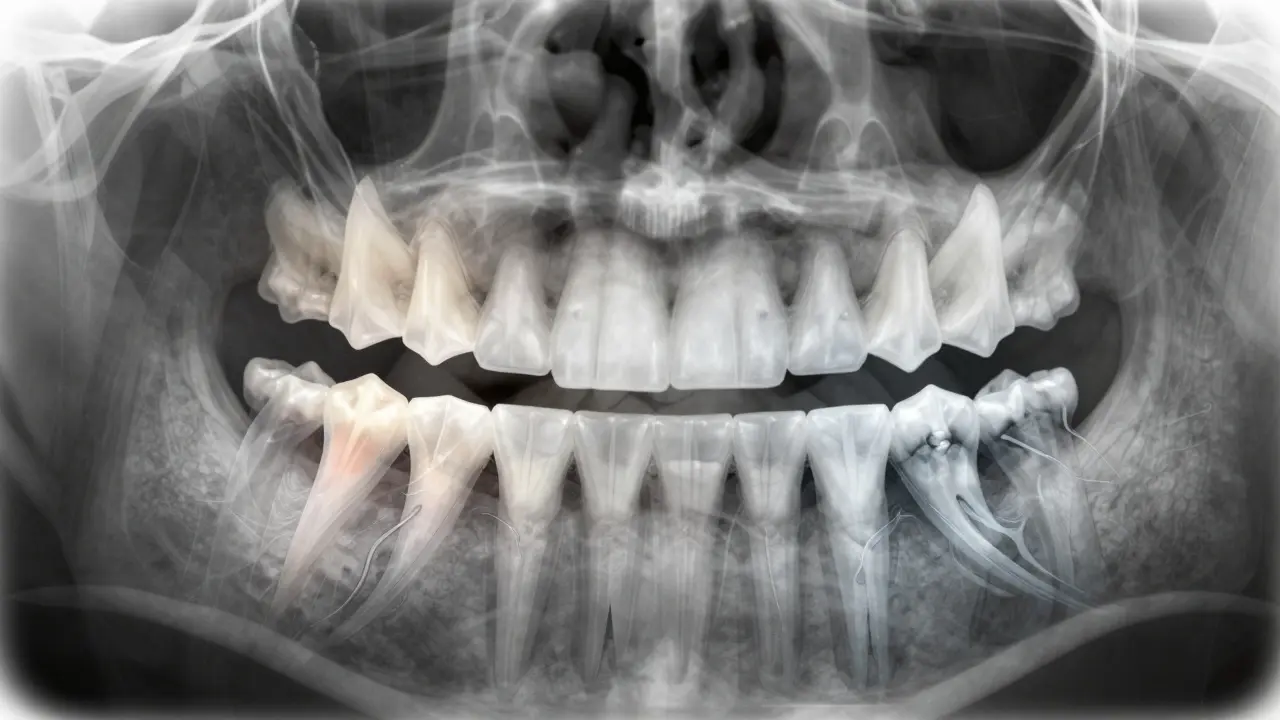

Nezapomeňte: mléčné zuby nemají předkořenky ani třetí moláry. To je důležité, když se díváte na RTG snímek dítěte. Když vidíte zub s třemi kořeny, a je to 6leté dítě - není to normální. To je buď trvalý zub, nebo nějaký výjimečný případ.

Nejlepší způsob, jak si zapamatovat názvy zubů, není zpěv nebo tabulky. Je to praktická praxe. Když se díváte na pacienta, řekněte si nahlas: „Horní pravý první molár - FDI 16“. Když děláte ortopantomogram, označte každý zub hned, jak ho vidíte. Používejte modely. Hrajte si s kamarády: „Který zub je 45?“ - a pak se podívejte na model. Každý den, kdy to uděláte, se to vám zapíše do mozku hluboko.

Ještě jeden trik: všimněte si, že v horní čelisti jsou zuby širší a větší než v dolní. To platí zejména pro moláry. A špičky v horní čelisti jsou vždy o něco delší než v dolní. To je užitečné, když se snažíte rozpoznat, který zub je který, když se díváte na RTG.

Ne. Řezáky a špičky mají obvykle jeden kořen. Předkořenky mají obvykle jeden, ale někdy dva. Kořenky mají v horní čelisti tři kořeny (u prvního moláru), ve dolní čelisti obvykle dva. Třetí molár může mít i tři nebo čtyři kořeny - a to se liší od člověka k člověku. To je důvod, proč je důležité dělat RTG před každou kořenovou léčbou.